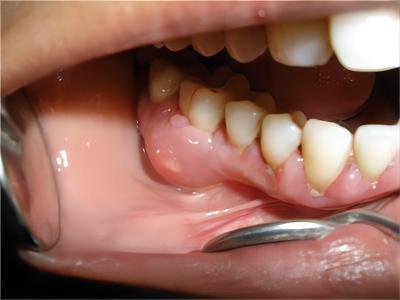

牙龈炎是发生于牙龈组织的炎症,患者可出现牙龈出血伴肿胀、发红、正常形态改变和偶尔不适等症状。本病主要由口腔卫生状况差导致,包括口腔不洁、牙菌斑等,诊断依据临床检查,治疗包括专业牙齿清洁和加强家庭口腔卫生。

牙龈炎可先引起牙齿与牙龈之间的沟(龈沟)加深,然后牙龈充血,炎症围绕一个或多个牙齿,伴牙龈乳头肿胀和易出血。一般无痛,可自行消退,也可维持轻度炎症数年。